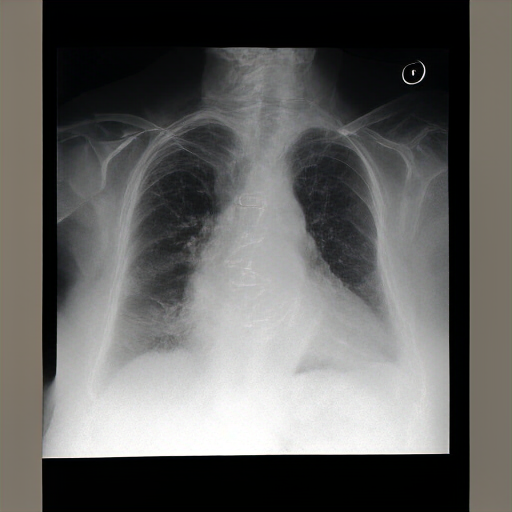

There are moderate-to-severe vascular congestion as well as perihilar opacification on the left than on the right. There is indistinctness of pulmonary vessels, suggestive of small-to-moderate pulmonary edema. There is no pneumomediastinum, a new small-to-moderate right-sided pleural effusion has not changed allowing for somewhat. There is no definite pneumothorax. A dialysis catheter has been removed.

Severe cardiomegaly is present. Previous mediastinal widening has improved. A region of consolidation, more discrete at the right base and in the left lower lobe, presumably with long-standing infection, is noted. There is increased vascular engorgement. No pulmonary edema is seen. Mediastinal vascular engorgement is present. A dual-channel hemodialysis catheter is at the cavoatrial junction, and atrial node tubes are in place.